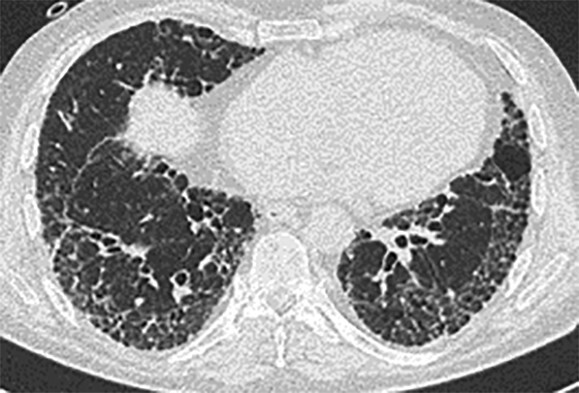

- Ein HRCT-Verlauf eines Patienten vor, während und nach einer akuten Exazerbation bei bestehender IPF ist in Abb. 36.4 dargestellt.

Abb. 36.4 Akute Exazerbation einer idiopathischen Lungenfibrose (AE-IPF) und akuter interstitieller Pneumonie (AIP).

Radiologie (mit freundlicher Genehmigung von Prof. Heussel und Prof. Kreuter, Thoraxklinik Heidelberg).

a 3 Monate vor der akuten Exazerbation zeigt sich radiomorphologisch ein milde ausgeprägtes mögliches „UIP-Muster“. (Quelle: Prof. Heußel und Prof. Kreuter, Thoraxklinik Heidelberg)

b Zum Zeitpunkt der AE-IPF finden sich ausgedehnte bilaterale Milchglasverschattungen und Konsolidierungen. (Quelle: Prof. Heußel und Prof. Kreuter, Thoraxklinik Heidelberg)

c 6 Monate nach der AE-IPF zeigt sich eine deutliche Zunahme der fibrotischen Veränderungen mit nahezu kompletter Rückbildung der Milchglasveränderungen. (Quelle: Prof. Heußel und Prof. Kreuter, Thoraxklinik Heidelberg)